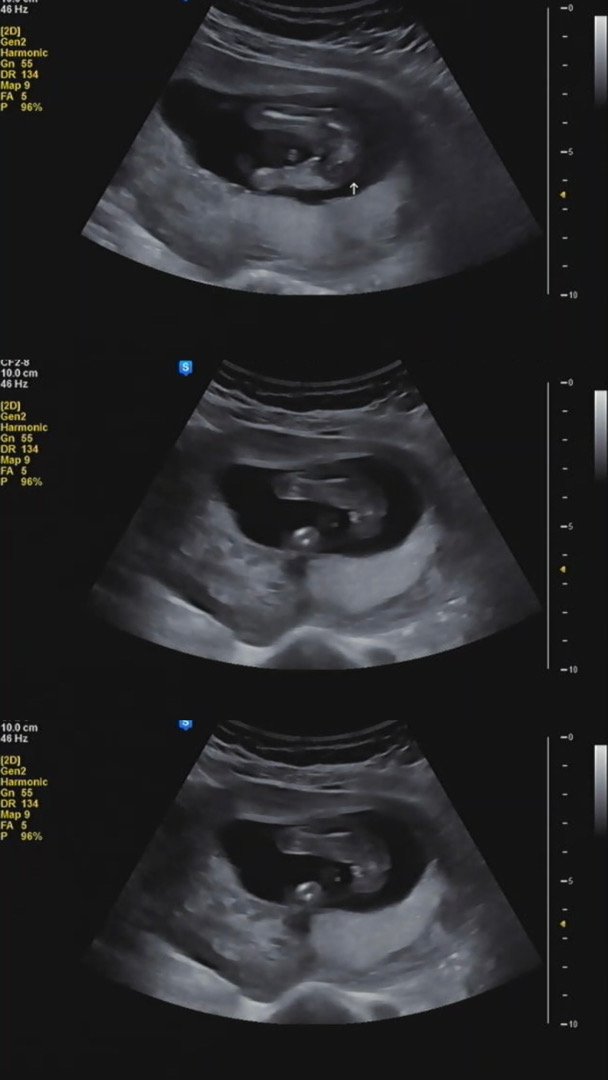

15주6일 다리사이 봐주실 분!

제가 보기에는 다리사이에 저 뭉툭한게 🌶️같은데 원장님은 아직 확실하지는 않지만 딸같다고 하셔서 헷갈리네요…!!!! 아들같나요 딸같나요 ㅎㅎ

저두 딸이요 아들은 확실하게 보여욧 🌶️

12주에 봤는데 헷갈리지도 않을정도로 뙇 고추더라고요 딸인듯합니다^^